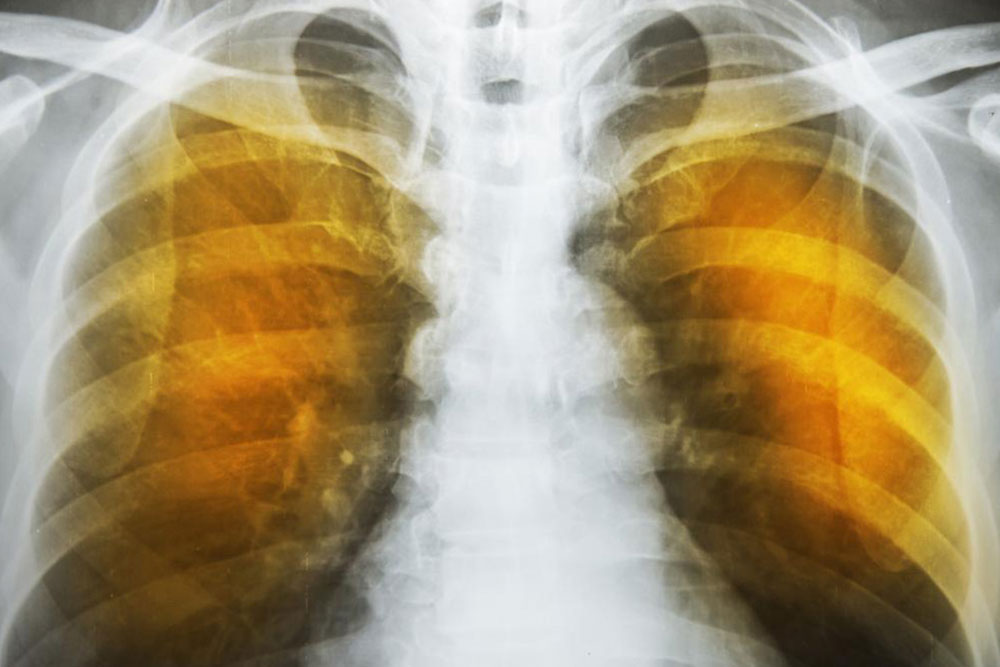

Emphysema is an oppressive respiratory disorder which results from the disintegration of the alveoli, i.e., the tissues where the interchange of gas with blood takes place. Destruction in any large scale will reduce the gas transfer area and the process of gas transfer itself, leading to oxygen starvation or hypoxia. When conventional treatment with bronchodilators, corticosteroids etc. have ceased to give relief, one has to resort to a method known as Long Term Oxygen Therapy or LTOT.